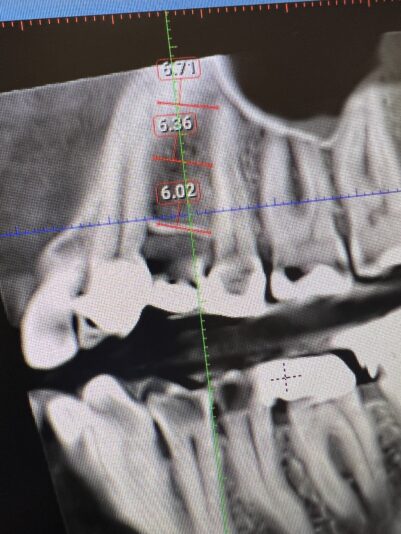

Hi everyone. I am new to placing implants and have been planning some cases and a couple have made me question what the proper plan should be.

Case #1 patient has limited mesiodistal space. Nearing 6mm. It is #5 location. My main concern is obviously lack on space but also what size implant is appropriate for certain teeth. This area has…